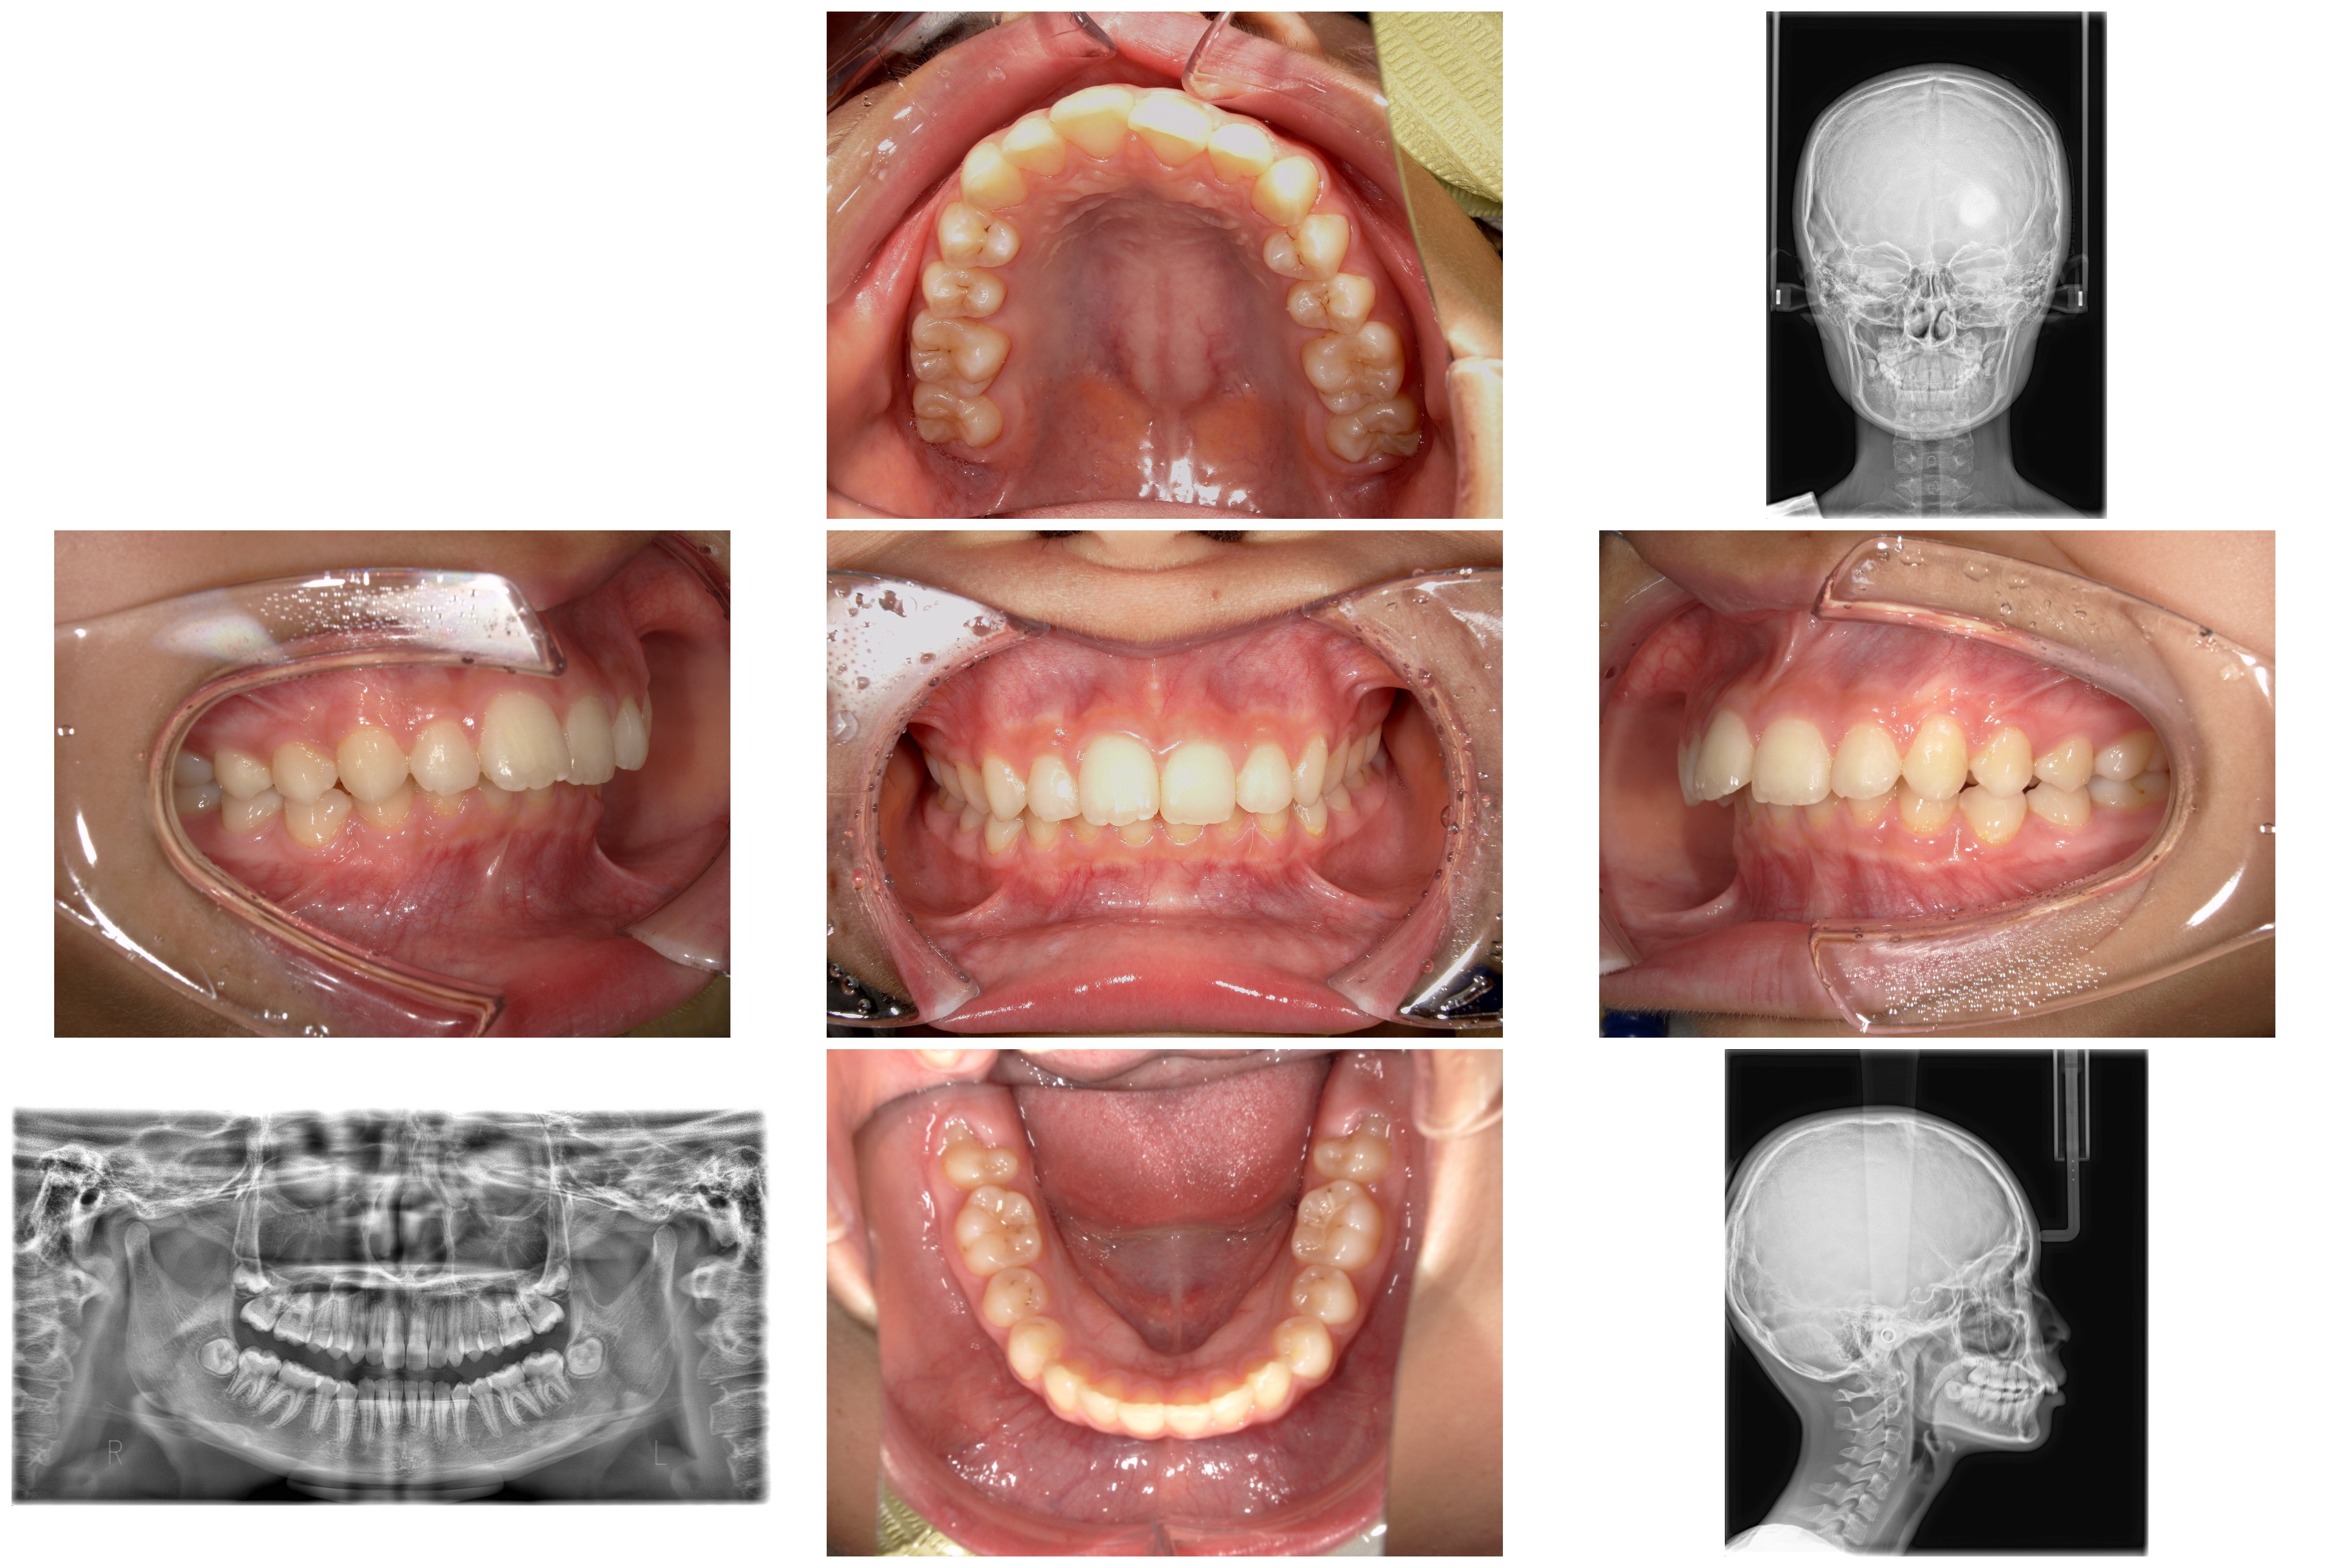

2. ご来院時の状態と診断

精密検査の結果、単なる「前歯の傾き」だけではない、骨格や奥歯の生え方に由来する複雑な要因が明らかになりました。

【検査結果の詳細】

軟組織:横顔を確認すると、口元が前に出て見える「凸型の横顔」でした。

骨格:上あごに比べて下あごが後ろに位置している骨格で、いわゆる出っ歯になりやすい骨格のタイプでした。また、咬む力が強く、顔の縦の長さがやや短い傾向がある骨格の特徴もみられました。

歯系: 前歯の前後的な差が著しく大きい「著大なオーバージェット」と、下の前歯が上の前歯に深く隠れてしまう「過蓋咬合(かがいこうごう)」が認められました。

大きな問題点: 本来なら生えきっているはずの下顎左右の第二大臼歯(一番奥の7番目の歯)が、萌出時期を過ぎても歯ぐきに埋まったままの「半萌出状態」となっていました。

上下の歯を咬み合わせたときに、上の前歯が下の前歯を深く覆いすぎてしまっている状態。放置すると下の前歯が上の歯ぐきを傷つけたり、将来的な顎関節症のリスクを高めたりすることがあります。